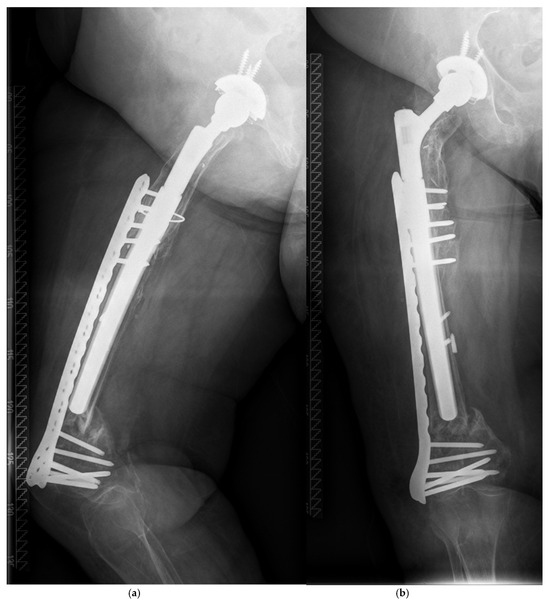

| Patient, Age at Surgery (ys.), Gender | Indication # | Bone Defect Paprosky et al. | Approach § | BMI (kg/m2) | Diabetes (y/n) | PPF Postop. (ys.) | Vancouver Classifi-cation | Conservative (C) vs. Operative Therapy (O) | Stem/Recon-Struction Length/Diameter (mm) * |

|---|---|---|---|---|---|---|---|---|---|

| 77, f. | TSR | 4 | TG | 20.8 | y | 4.2 | C | O (ORIF by Plate) | 290/14 |

| 68, f. | AL | 2B | TG | 22.5 | n | 0.8 | C | O (ORIF by Plate, Liss ©) | 250/18 |

| 73 +, f. | AL | 3B | TG | 34.4 | n | 8.6 | C | O (MIS by Plate, VA ©) | 290/21 |

| 75, f. | AL | 2B | TG | 25.9 | n | 9.8 | C | O (ORIF by Plate, VA ©) | 250/19 |

| 76, f. | AL | 2A | TG | 31.8 | n | 0.1 | B1 | O (ORIF by Plate, Liss ©) | 240/22 |